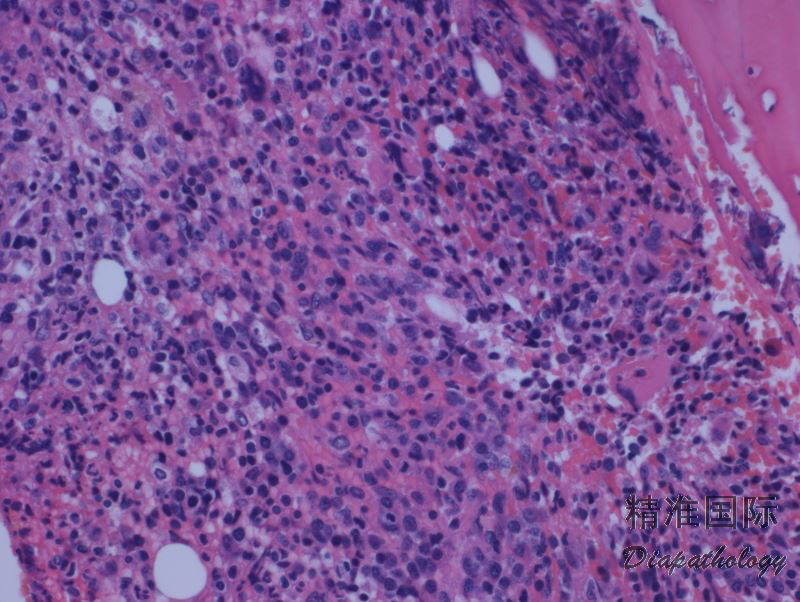

肿瘤细胞形态大小多样,但急性型具有典型的细胞形态(多数患者在病程某阶段表现为急性型),其特点是多叶状细胞核如花瓣样,称为花样细胞;染色质致密、深染,但花样细胞通常无明显核仁;胞质嗜碱性,可见胞质空泡。有的病例(主要是慢性和闷燃型)淋巴细胞大小形态可类似正常淋巴细胞。